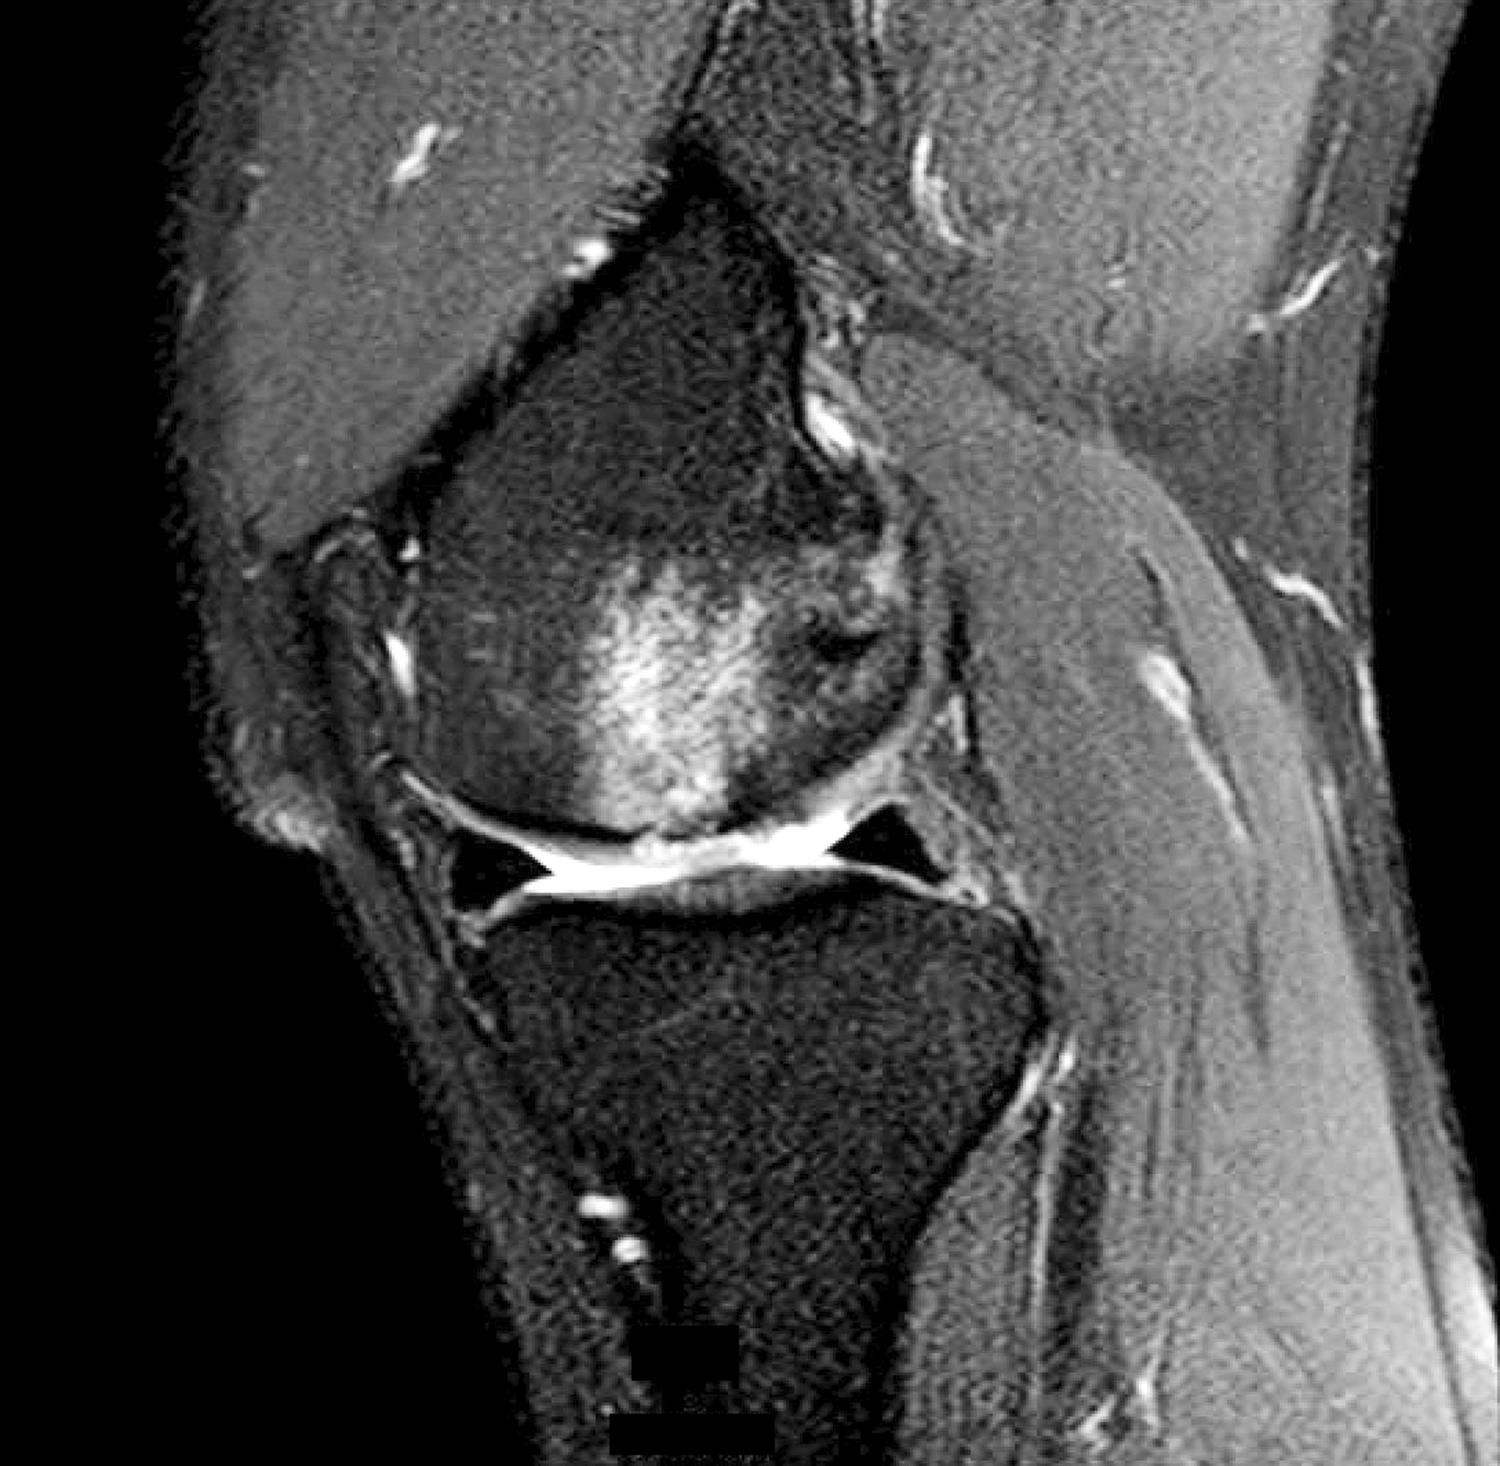

Osteochondral defect, knee Radiology at St. Vincent's University Hospital Knee Cartilage Defect Cartilage injuries are quite common, especially among athletes, with a suggested overall prevalence as high as 36% in knees. Articular cartilage defects of the knee comprise of a spectrum of disease entities from single, focal defects to advanced degenerative disease of. Cartilage loss in the knee can lead to complications like bone spurs, cysts, and lesions. Cartilage damage is most. Knee Cartilage Defect.

Typical MRI appearance of an osteochondral defect in the knee (a Knee Cartilage Defect Articular cartilage defects of the knee comprise of a spectrum of disease entities from single, focal defects to advanced degenerative disease of. Cartilage damage is most frequently seen between the ages of 15 and 30 or above the age of 50. Both types of knee cartilage can get torn and may cause symptoms like knee pain, buckling of the knee. Knee Cartilage Defect.